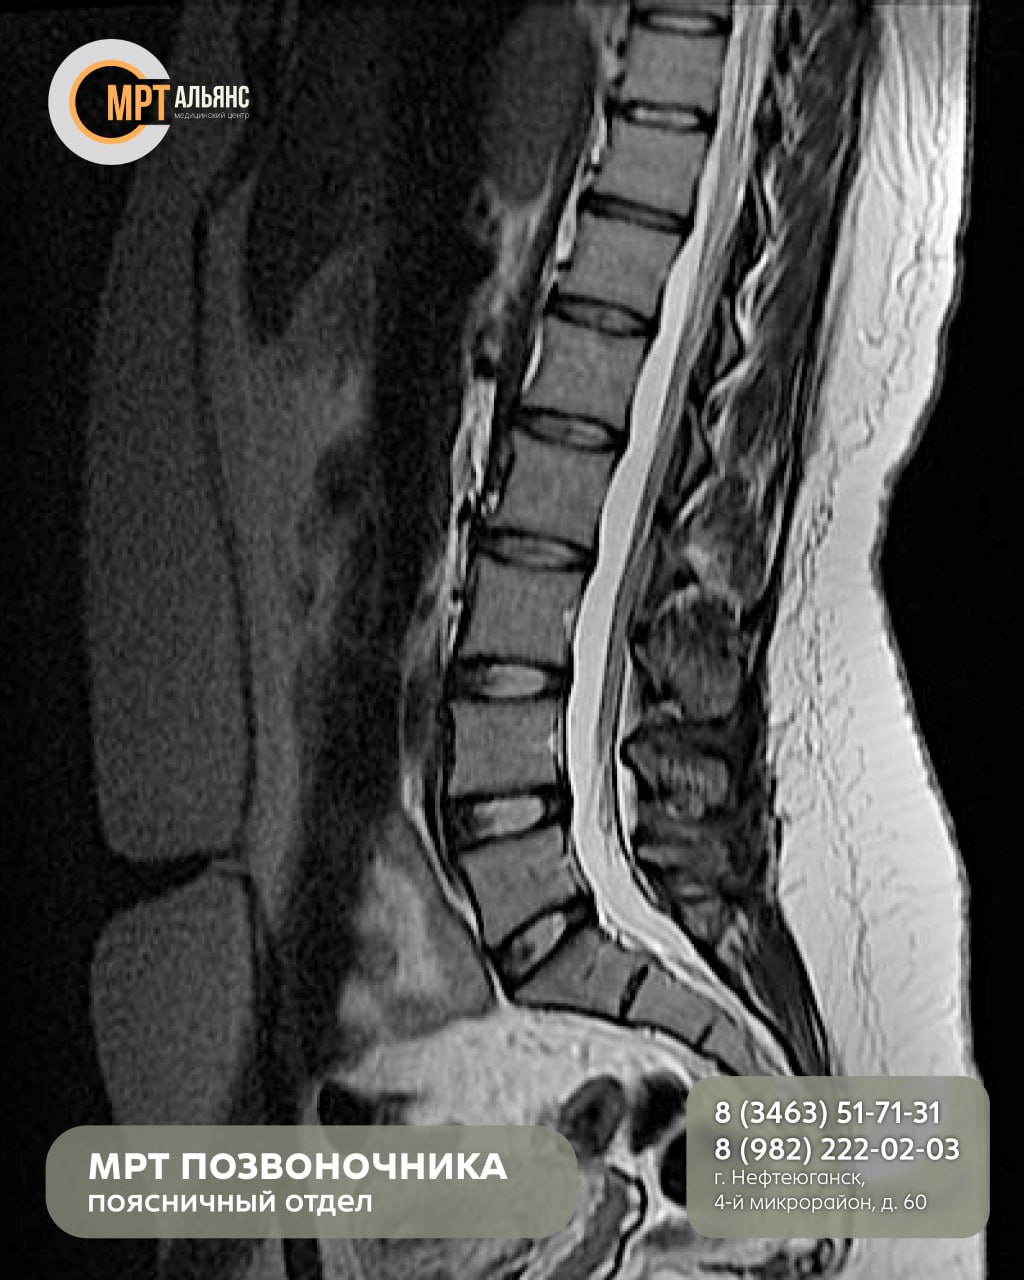

•Грыжи и протрузии межпозвонковых дисков

•Остеохондроз

•Травмы и смещения позвонков

•Артрит, артроз, стеноз

•Воспалительные процессы (болезнь Бехтерева)

МРТ идеально визуализирует мягкие ткани: спинной мозг, нервные корешки, межпозвонковые диски и связки. Идеально, когда КТ или рентген не дали четкой картины.